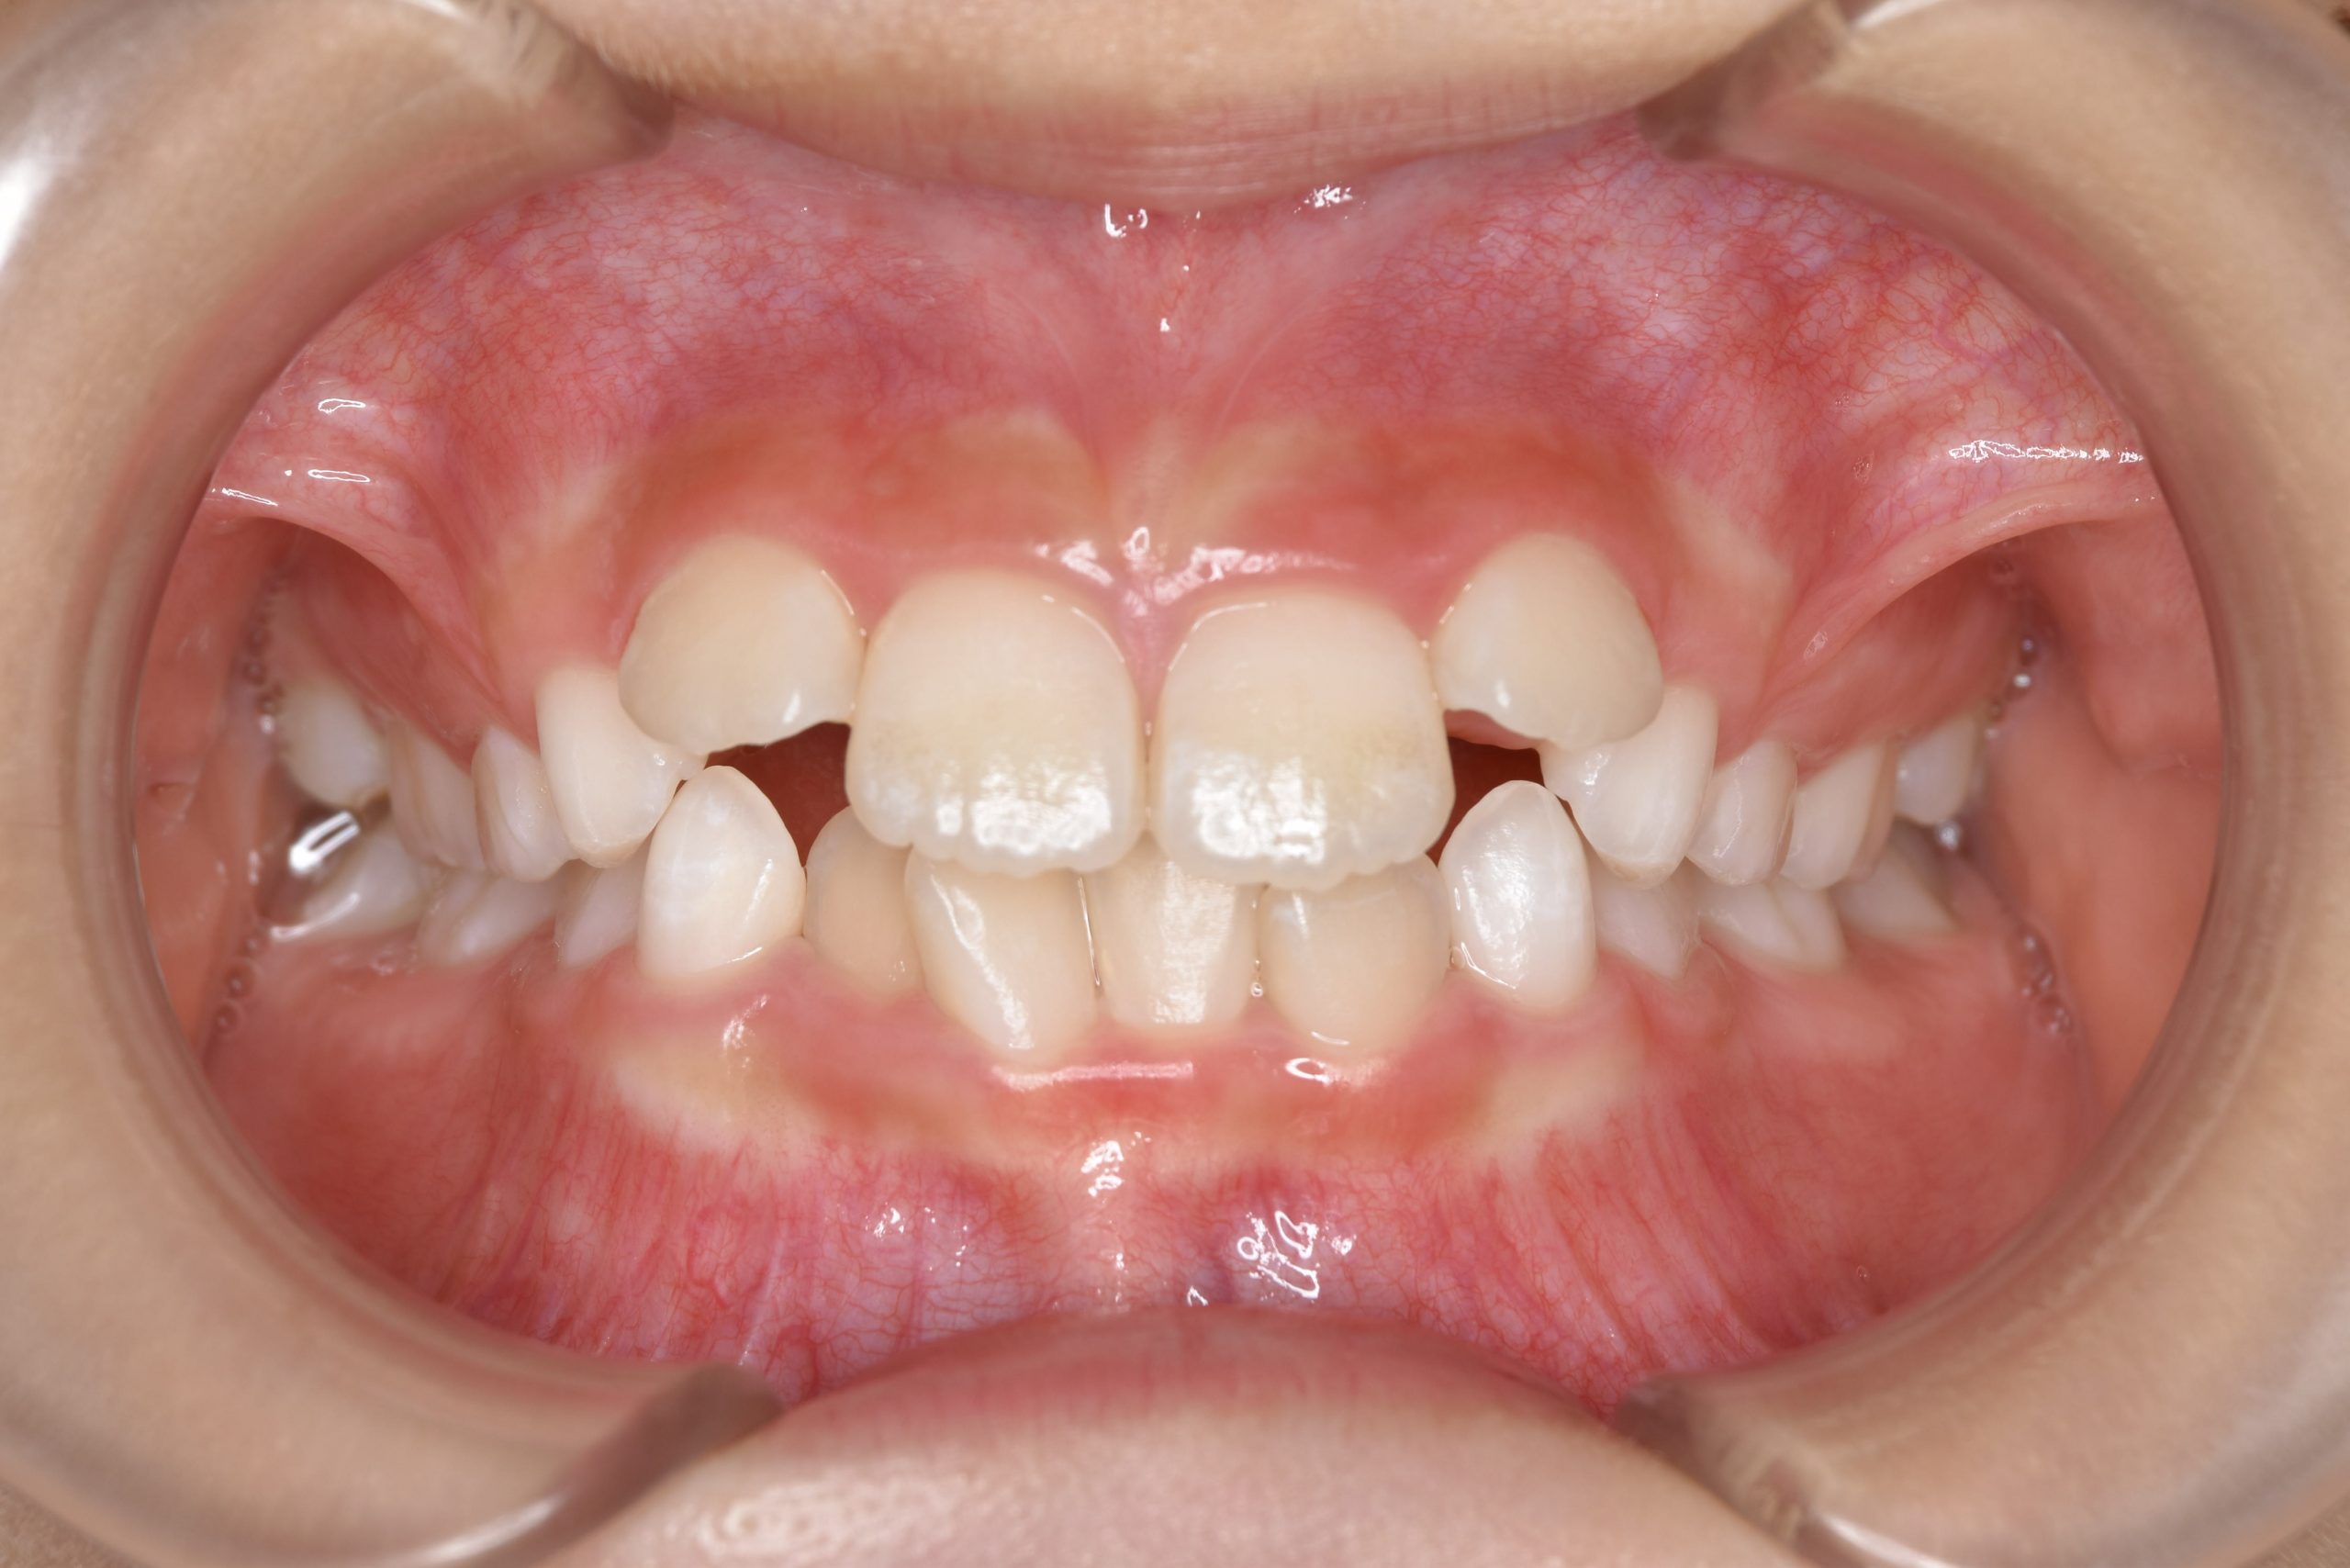

全顎ワイヤー矯正 症例_610 Case

ビフォー

| 主訴 | 前歯の歯並び|歯ぎしり |

| 施術内容 | 小児矯正1期治療 |

| 治癒期間 | 2年4か月間 |

| 費用 | 711,700円(税込) |

| リスク・副作用 | 違和感、不快感、痛み |